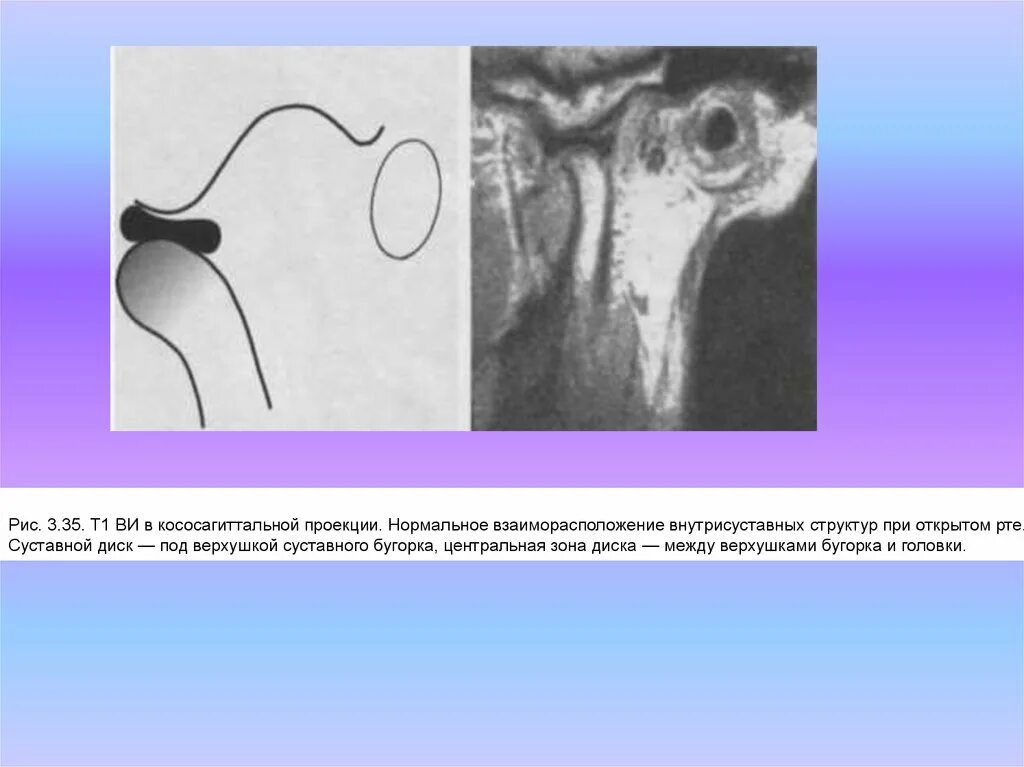

Уровень тольятти бугорок